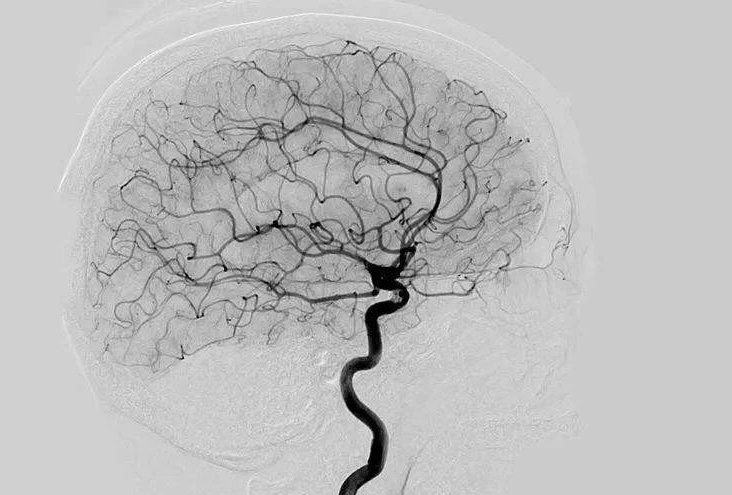

Digital Subtraction Angiography 血管造影機(jī)應(yīng)注意什么?

Digital Subtraction Angiography 血管造影機(jī)又稱數(shù)字減影血管造影機(jī),是通過電子計(jì)算機(jī)進(jìn)行輔助成像的血管造影方法,應(yīng)用計(jì)算機(jī)程序進(jìn)行兩次成像完成的。在注人造影劑之前,第一次成像工作,圖像轉(zhuǎn)成數(shù)字信號(hào)儲(chǔ)存,注人造影劑后,再次成像并轉(zhuǎn)換成數(shù)字信號(hào),兩次數(shù)字相減,消除相同的信號(hào),得到只有造影劑的血管圖像。臨床主要應(yīng)用于冠心病、心律失常、瓣膜病和先天性心臟病的診斷和治療。